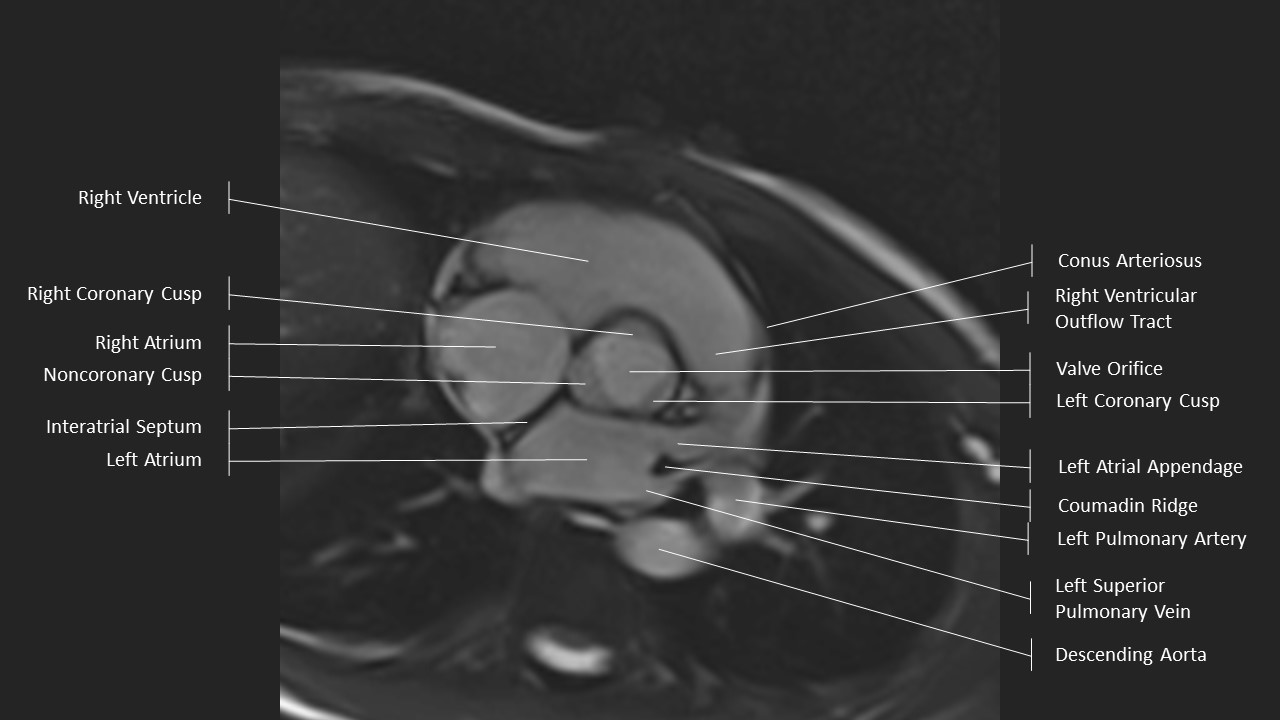

Aortic Root Series:

Aortic Valve in Systole

Aortic Root Series